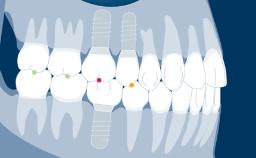

Implant impressions are important for the fabrication of dental prostheses. The aim of implant impressions is accurate transfer of the intra-oral implant situation to the dental laboratory. It is possible to record the implant situation with conventional analog impression techniques, or using digital technologies.

In the case of implant impressions, a precision-made impression component is used to register the position, alignment, and rotational orientation of the implant.

The impression, whether it follows a conventional (that is, analog) or digital workflow, then records this information in relation to the surrounding hard and soft tissues. This module will deal with conventional impression techniques and all of the parameters involved.